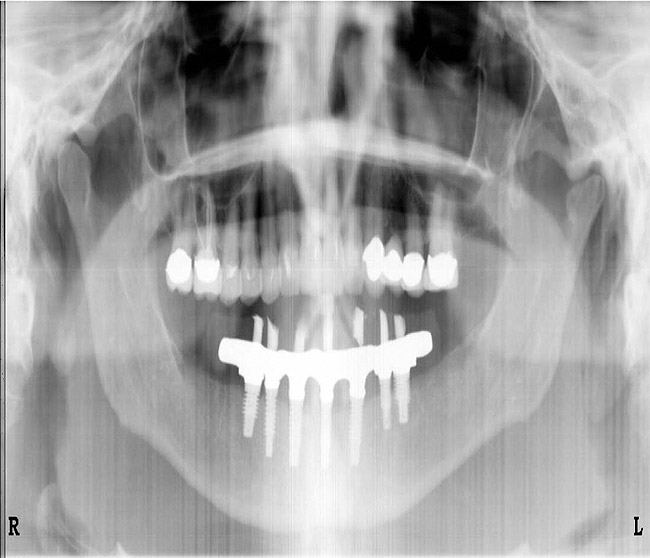

Figure 10c  Traditional fixed prosthodontics performed to level the opposing arch and regain sufficient crown height space.

Figure 10c

Figure 10d  Traditional fixed prosthodontics performed to level the opposing arch and regain sufficient crown height space.

Figure 10d